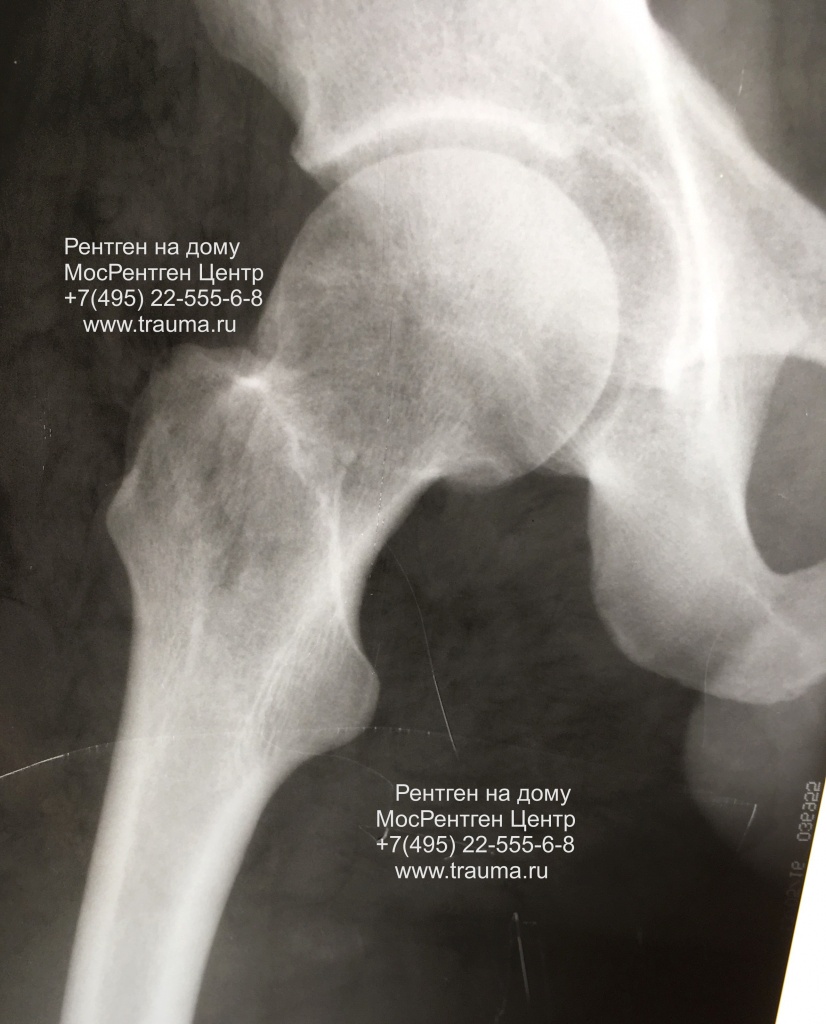

Рентген ТБС: Нормальные показатели